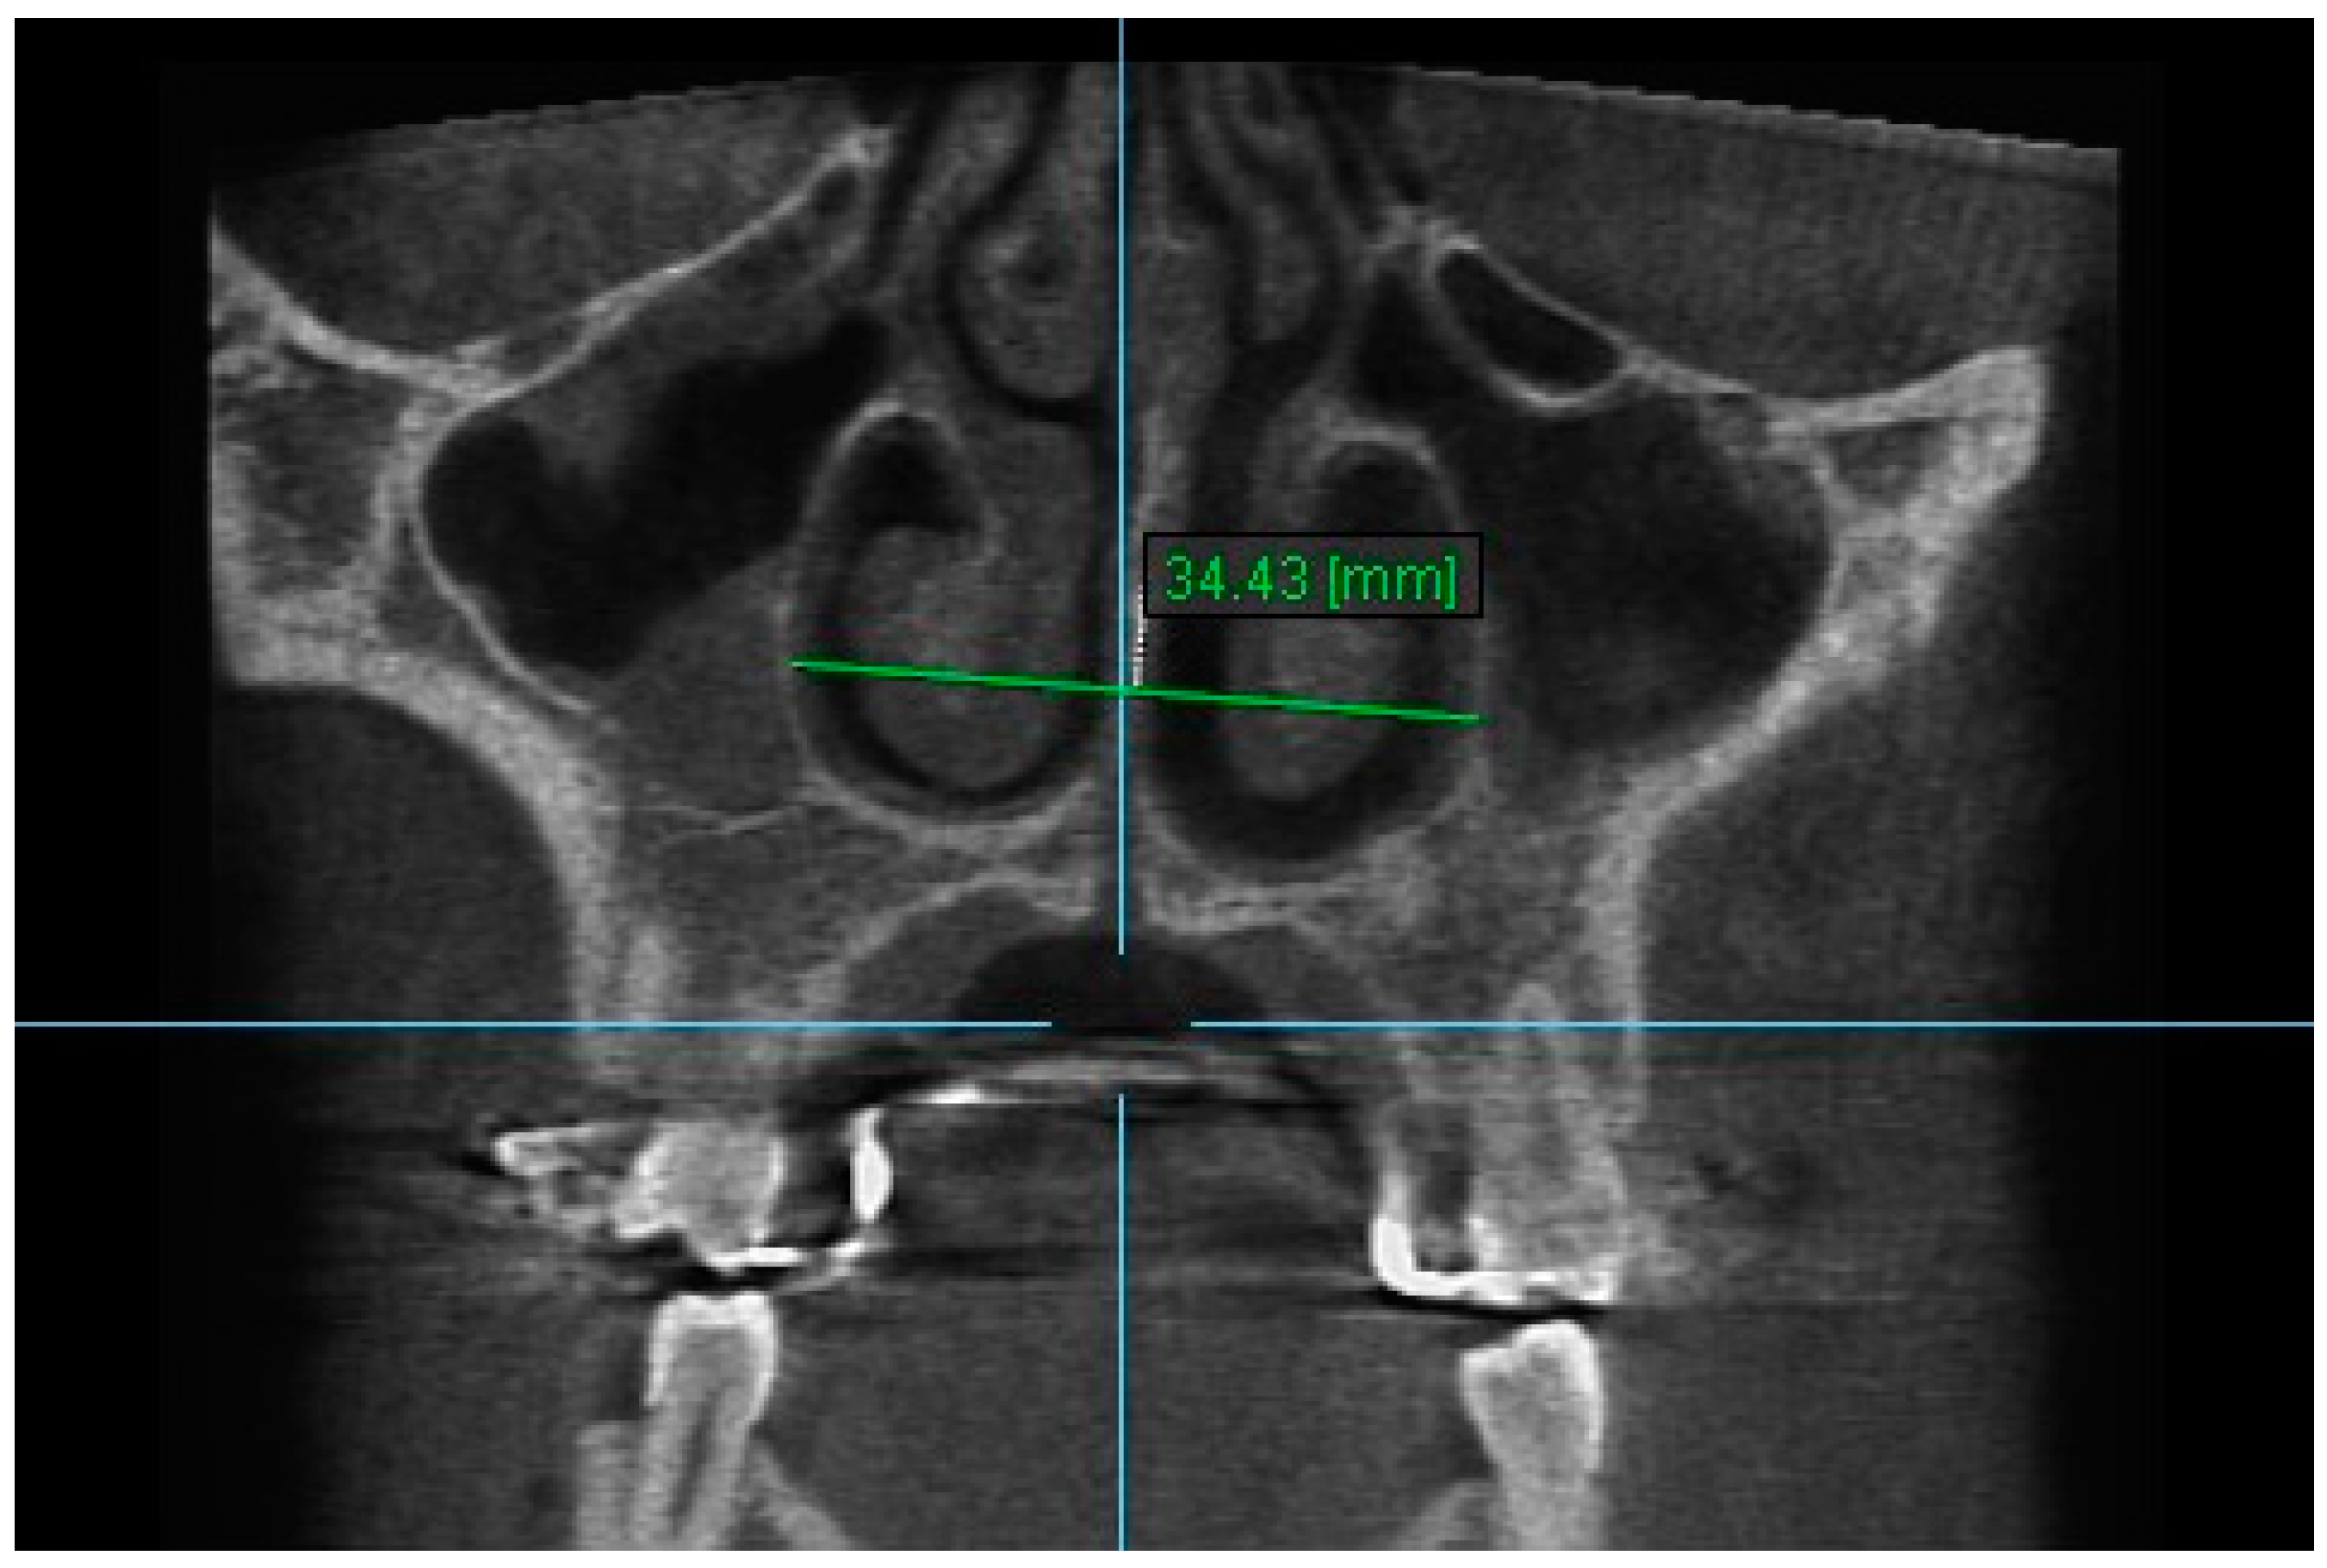

3. Nasal Width 3: The maximum lateral interior width of nasal cavity on coronal slice through the center of the mesial buccal root of the first premolar (Figure 5).

Figure 5.

Nasal Width 3.